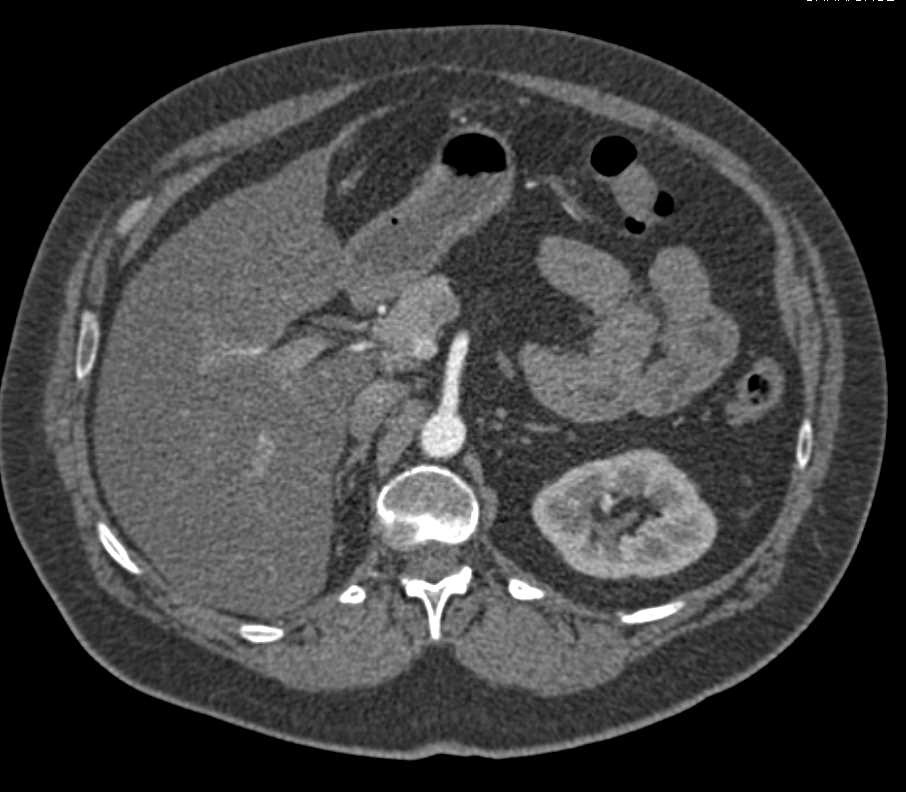

Carcinoma of the Body of the Pancreas with Fiduciary Clips